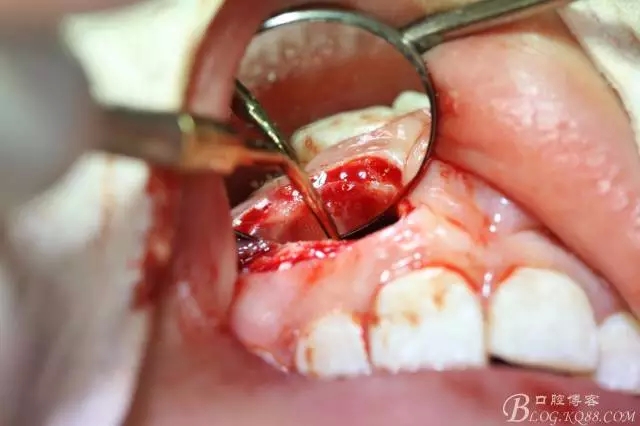

病例資料: 患者、柴xx、女、16歲。??茩z查及病歷如下圖: 患者同意我院正畸科建議,遂轉(zhuǎn)診倒外科。術(shù)前簽知情同意書。 治療過程: 圖1.術(shù)前的CBCT檢查:13阻生,疑為含牙囊腫??v剖面顯示12牙根吸收至根尖1/3。 圖2.局部麻醉下 。行唇側(cè)弧形切口,12松動(dòng)不到1°。 圖3.翻瓣、暴露骨面。 圖4.去骨、 暴露13牙冠 圖5.去骨、逐漸顯露13。 圖7.拔除13. 圖8.摘除囊壁 圖9.必須完整剝離囊壁。 圖10.摘除囊壁后形成的骨腔 圖11.超聲骨刀12根尖倒預(yù)備 圖13. 消毒棉球骨腔內(nèi)隔濕血液,紙尖干燥倒預(yù)備好的根管 圖14. 紙尖無血即可 圖15。MTA倒充填 圖16.骨腔填塞膠原蛋白海綿 圖17.拔除的13及摘除的囊壁 圖18.縫合 圖19.術(shù)后x線根尖片影像:MTA封閉根尖